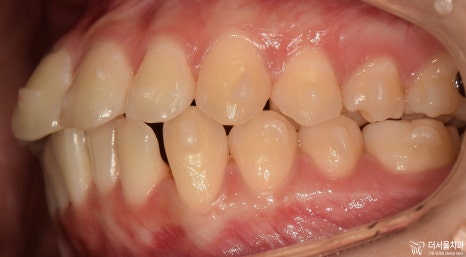

먼저 교합면에서 보게 되면, 앞니들의 총생이 관찰됩니다.

정면에서는 뭔가…. 그렇게 고르지 않은 치열이라는게 느껴지죠?

어색한 느낌이 계속 듭니다.

측면에서는 확연히, 돌출입 형태를 확인하실 수 있습니다. 이렇게 앞니들이 앞으로 뻐드러져

있는데 심미선을 기준 으로 봤을 때 입술의 위치가 그대로 예쁜 곳에 있는 걸 보면

연조직이 얇아서 가능하다라는 것을 추측할 수 있겠네요.